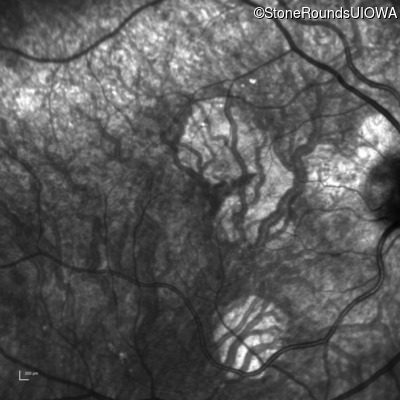

Infrared Fundus Photograph - Right - 20/20 -2 sc

Exemplar